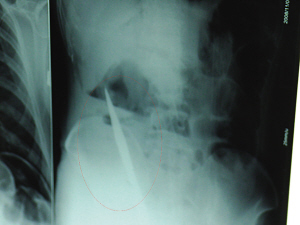

X光片上,尖刀清晰可見。

從男子體內(nèi)取出的尖刀足足有19厘米長(zhǎng)。

銅山一58歲男子因服毒被送到醫(yī)院搶救,可醫(yī)生采取搶救措施后卻發(fā)現(xiàn)效果不佳。后來經(jīng)細(xì)致檢查,醫(yī)生有了個(gè)驚人的發(fā)現(xiàn),該男子的體內(nèi)竟然有一把尖刀,醫(yī)生通過手術(shù)將位于其腹部右側(cè)橫結(jié)腸下緣的尖刀取了出來。這把尖刀足足有19厘米長(zhǎng)!據(jù)醫(yī)生推測(cè),這把刀應(yīng)該是從肛門推進(jìn)體內(nèi)的,不知男子為何想以如此殘酷的方式結(jié)束自己生命。由于搶救及時(shí),該男子已暫時(shí)脫離危險(xiǎn)。

6日上午,記者在徐州礦務(wù)集團(tuán)總醫(yī)院重癥監(jiān)護(hù)室見到了這名男子,目前他雖然已經(jīng)恢復(fù)了意識(shí),但還不能開口說話,需要呼吸機(jī)輔助呼吸。據(jù)醫(yī)生介紹,4日中午12時(shí)左右,這名男子因服毒輕生被緊急送到醫(yī)院進(jìn)行搶救,之前,這名男子已經(jīng)在當(dāng)?shù)剜l(xiāng)鎮(zhèn)醫(yī)院進(jìn)行了近20小時(shí)的治療,但效果不佳!安∪吮晦D(zhuǎn)院到礦總院時(shí)已神志不清,血壓極低,處于休克狀態(tài)!本茸o(hù)人員給男子洗胃、初步處理以后,發(fā)現(xiàn)男子呼吸急促,于是趕緊給他拍片檢查。結(jié)果讓所有的醫(yī)生大吃一驚,竟有一把尖狀異物橫在該男子腹腔內(nèi)!當(dāng)天下午5時(shí)30分,輕生男子被推上了手術(shù)臺(tái)。經(jīng)過40多分鐘的手術(shù),該男子腹腔被打開,手術(shù)醫(yī)生發(fā)現(xiàn),男子體內(nèi)的金屬狀異物竟然是一把長(zhǎng)19厘米的尖刀!

醫(yī)生告訴記者,手術(shù)后,醫(yī)生在病人身上并未發(fā)現(xiàn)刀痕,最后,經(jīng)過檢查發(fā)現(xiàn),在該男子直腸處找到穿孔。醫(yī)生從醫(yī)學(xué)角度分析后認(rèn)為,這把尖刀應(yīng)該是從肛門插入直腸的。醫(yī)生說,因?yàn)椴∪藫尵燃皶r(shí),尖刀并未傷及要害,所以暫時(shí)保住了性命,但后期可能會(huì)出現(xiàn)腹腔感染、AIDS、器官衰竭等多種并發(fā)癥。